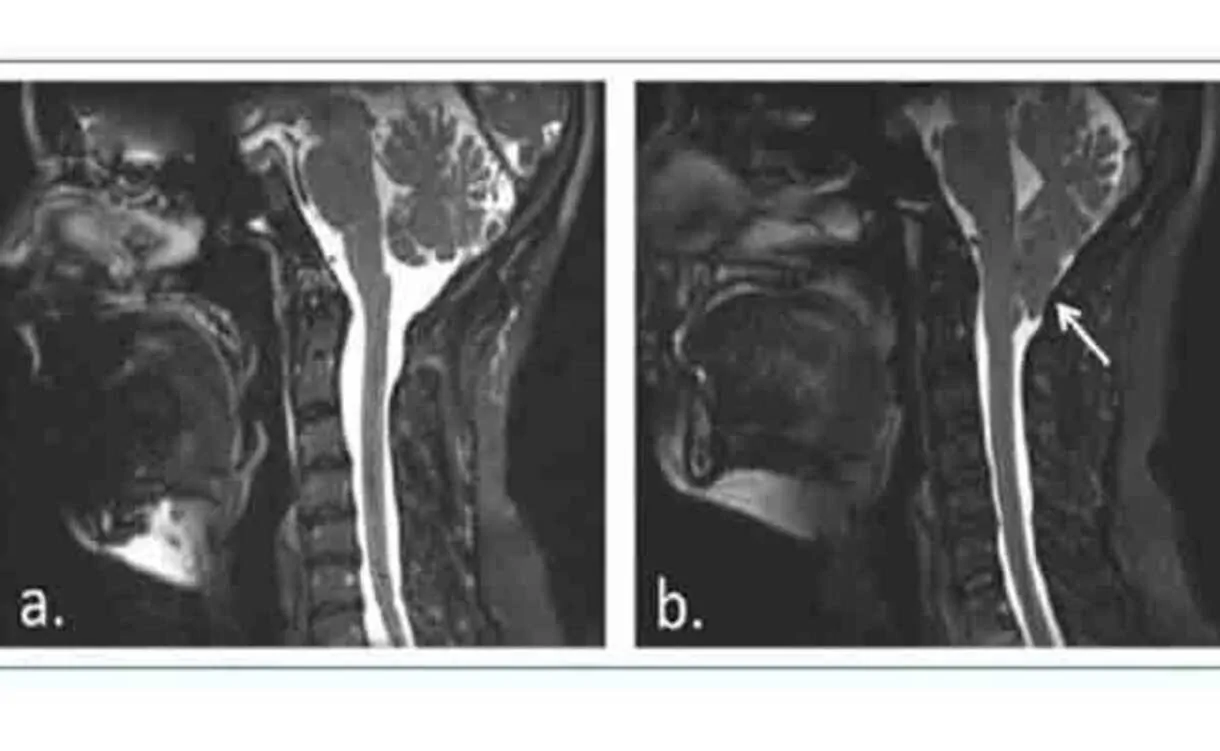

متلازمة ما بعد الارتجاج ليست ضررًا هيكليًا في الدماغ، بل هي ضرر وظيفي. بمعنى آخر، هي إصابة دماغية غير مرئية. من الوهلة الأولى يبدو الشخص الذي يعاني متلازمة ما بعد الارتجاج طبيعيًا: يمكنه المشي، الكلام، الدراسة، العمل. لا يتخيل أحد أنه يمر بوقت عصيب.

بالمثل، أن تبدو جميع مناطق الدماغ طبيعية بعد الارتجاج (كما هو الحال غالبًا عند فحص صور التصوير العصبي)، لا يعني أن هذه المناطق تعمل معًا بشكل جيد، ولا أنها تسمح بالوظيفة والتواصل الدماغي اللازم لأداء الشخص بشكل أمثل في حياته اليومية.

إذًا، لا يتم اكتشاف متلازمة ما بعد الارتجاج عبر اختبارات التصوير العصبي التقليدية لأن نسيج الدماغ لا يظهر تضررًا واضحًا أو مرئيًا كما هو الحال عند تصوير ورم دماغي أو سكتة دماغية.

ما اكتشفته الأبحاث الحديثة بخصوص متلازمة ما بعد الارتجاج هو أن السلامة الهيكلية للخلايا العصبية تظل محفوظة (ولهذا لا تُرى تغيّرات في التصوير العصبي)، ومع ذلك، ما تَضرر هو قدرة الخلايا العصبية على الإشارة إلى الأوعية الدموية لكمية الدم المناسبة التي تحتاجها لأداء نشاطها.